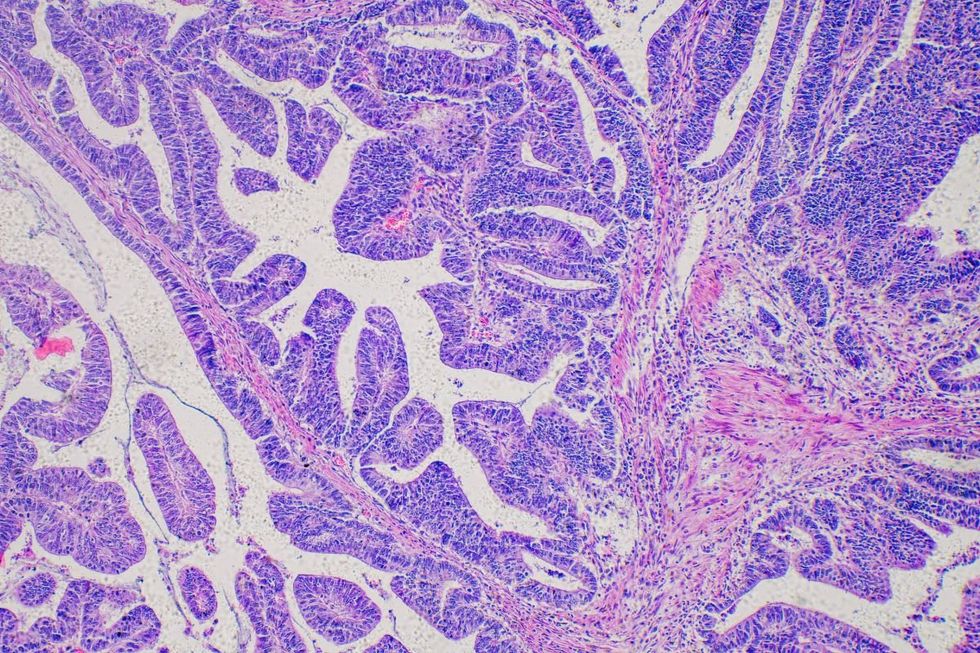

Barrett’s Oesophagus can lead to oesophageal cancer